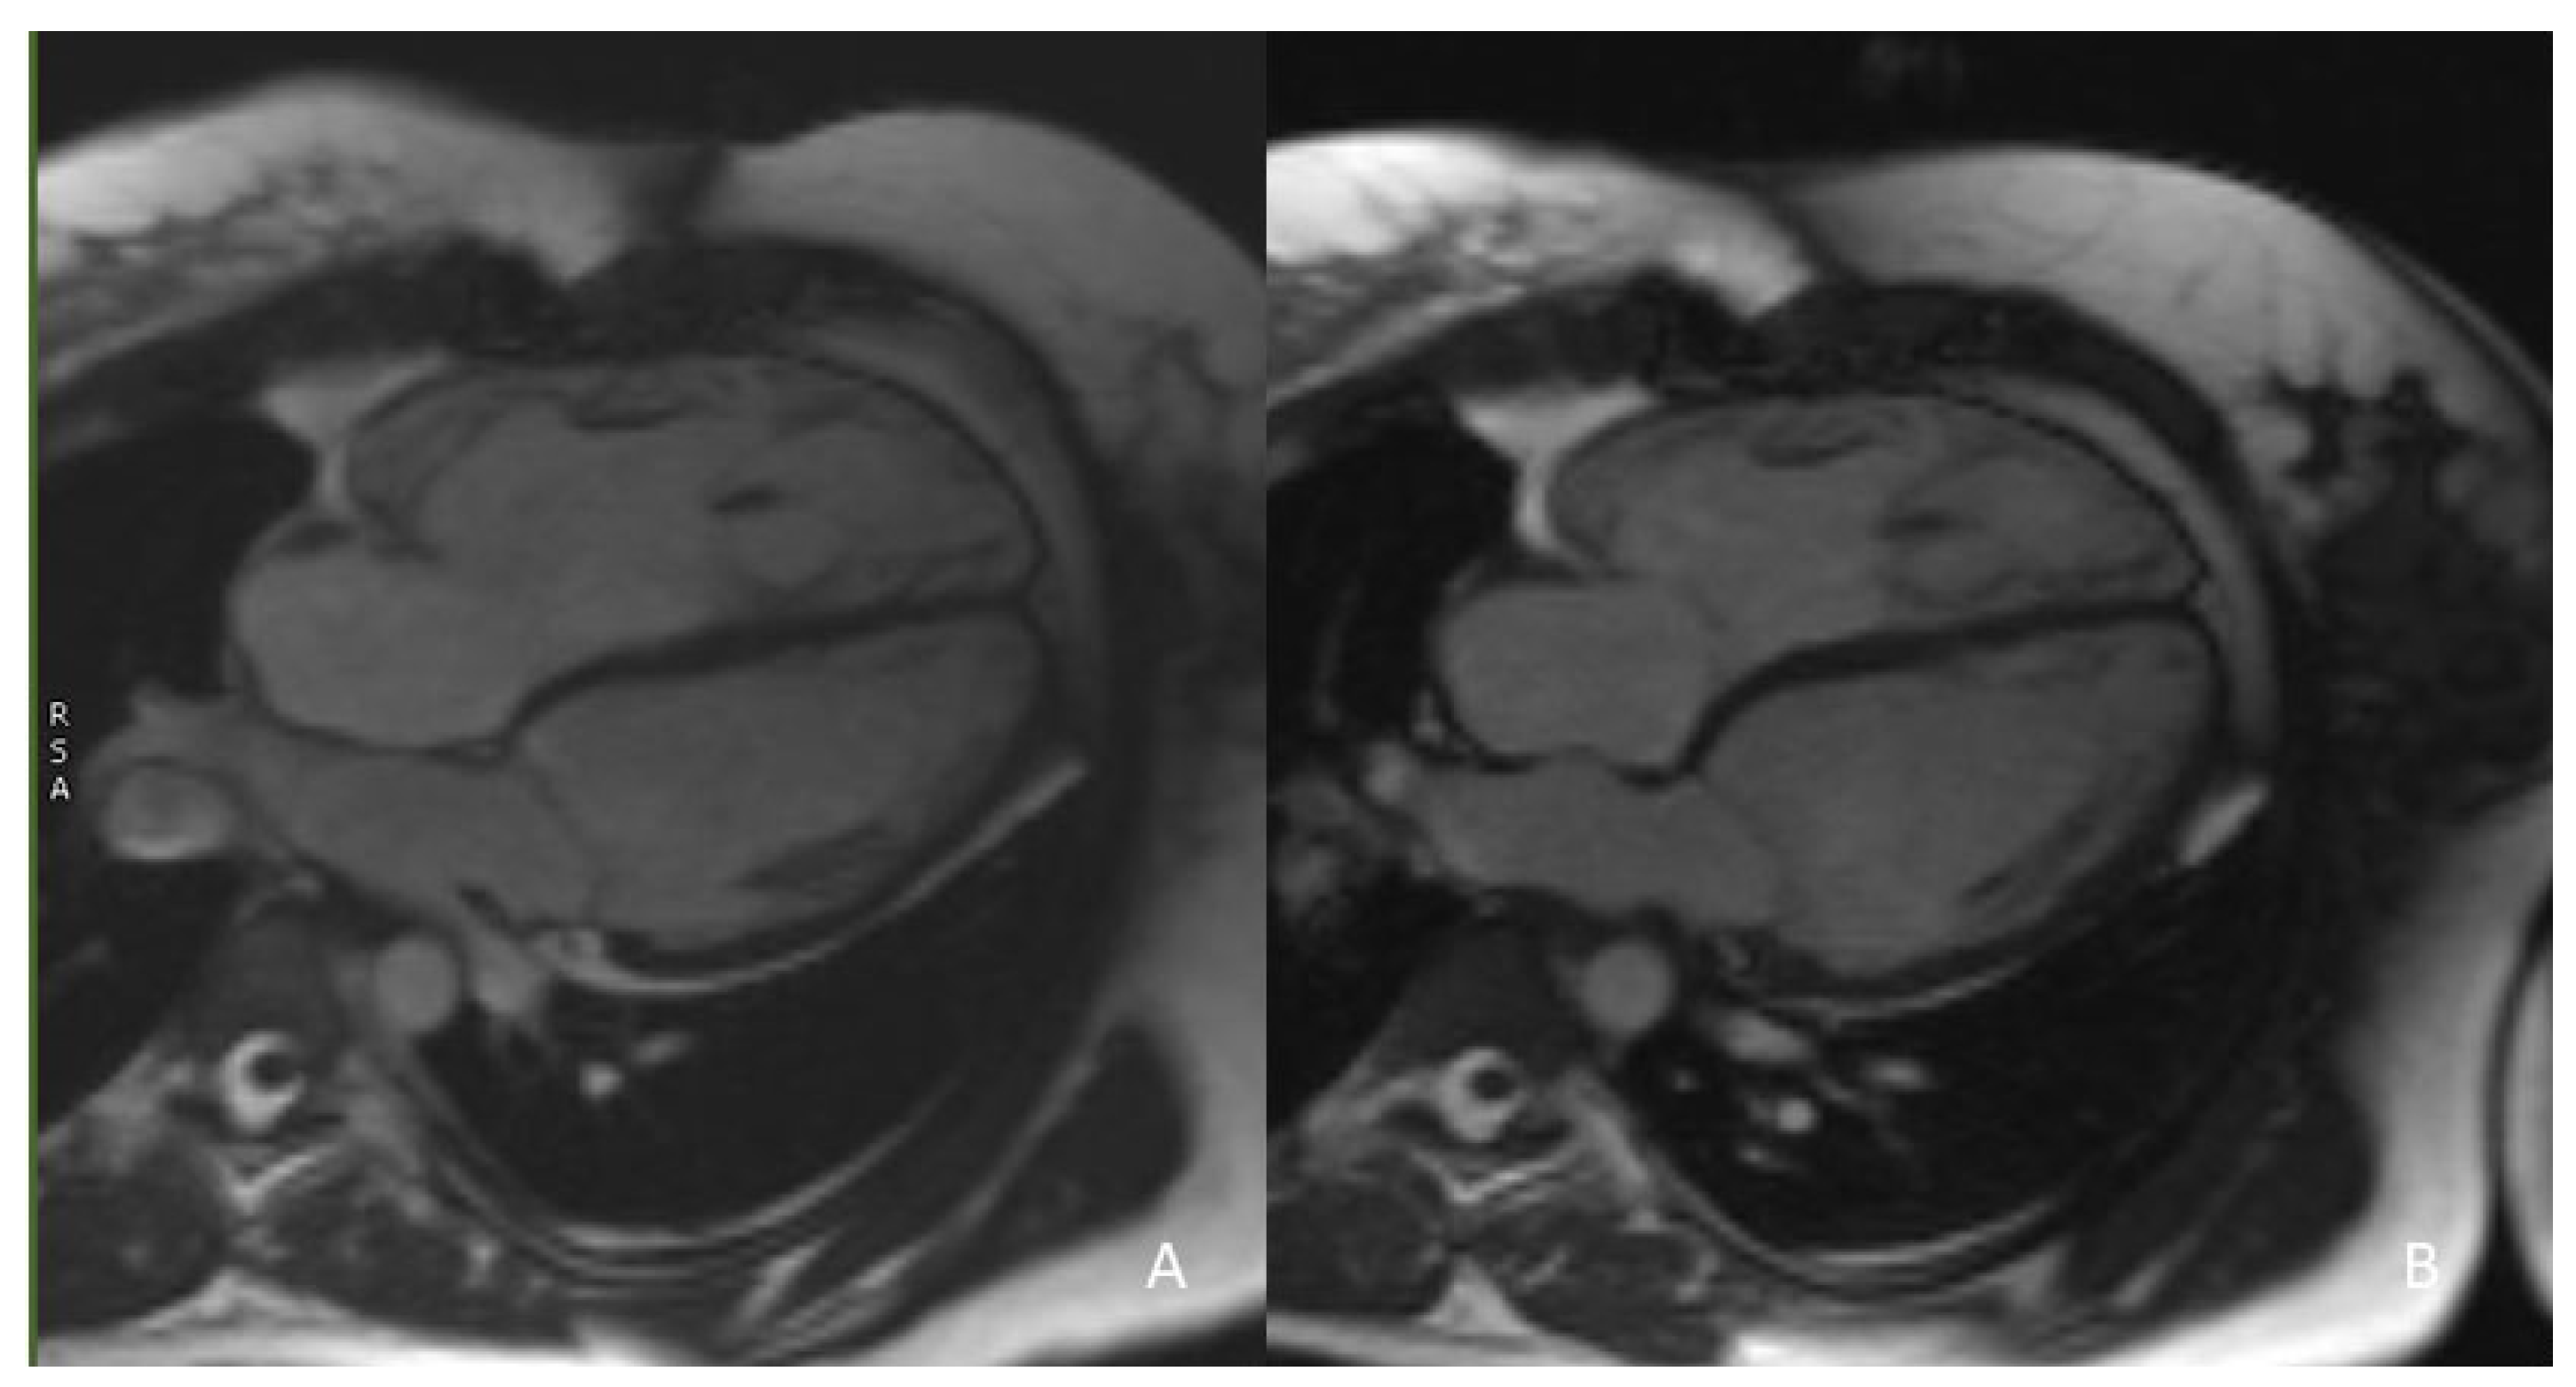

CMR is currently considered the gold standard for ventricular volume quantification and the assessment of systolic function. A reduction in RV volume overload has been shown in CMR studies after successful PPVI treatment; an example is given in Figure 1.

Figure 1.

(A) 32-year-old patient, male. Significant reduction in RV dilatation is evident after PPVI (B) in comparison to the previous CMR study before the procedure (A), as highlighted in this 4-chamber view cine.